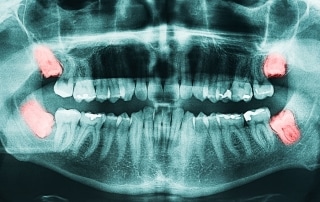

Slikanje zob

Slikanje zob z zobnim rentgenom je postalo sestavni del sodobnega zobozdravstva. Zobozdravnik na...